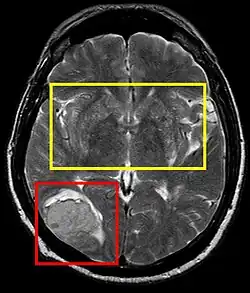

![]() | |

| Stroke brain (similar to cerebral softening) | |

Cerebral softening, also known as encephalomalacia, is a localized softening of the substance of the brain, due to bleeding or inflammation. Three varieties, distinguished by their color and representing different stages of the disease progress, are known respectively as red, yellow, and white softening.[1][2]